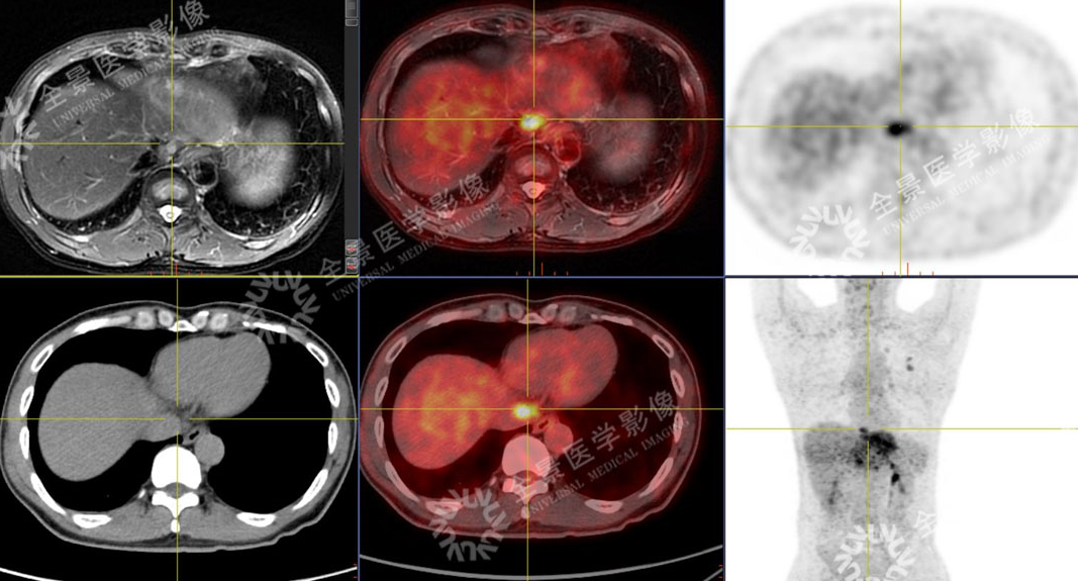

男性,57岁,上腹疼痛2月余,加重1周。外院CT:肝左叶占位。既往有乙肝病史多年。

SUVmax=4.59

PET示:腔静脉裂孔处结节FDG摄取增高;

CT示:无明显异常密度影。

怀疑:腔静脉癌栓?后心膈角区淋巴结?

确诊:腔静脉癌栓